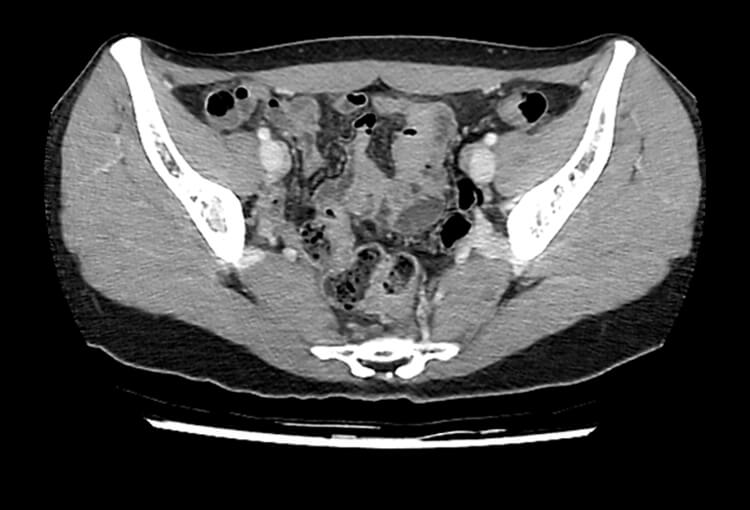

Before and After Denoising

120 kV / 30 mAs / 1mm

Before FBP (Noise 150) VS After ClariCT.AI (Noise 49) 67% Denoising